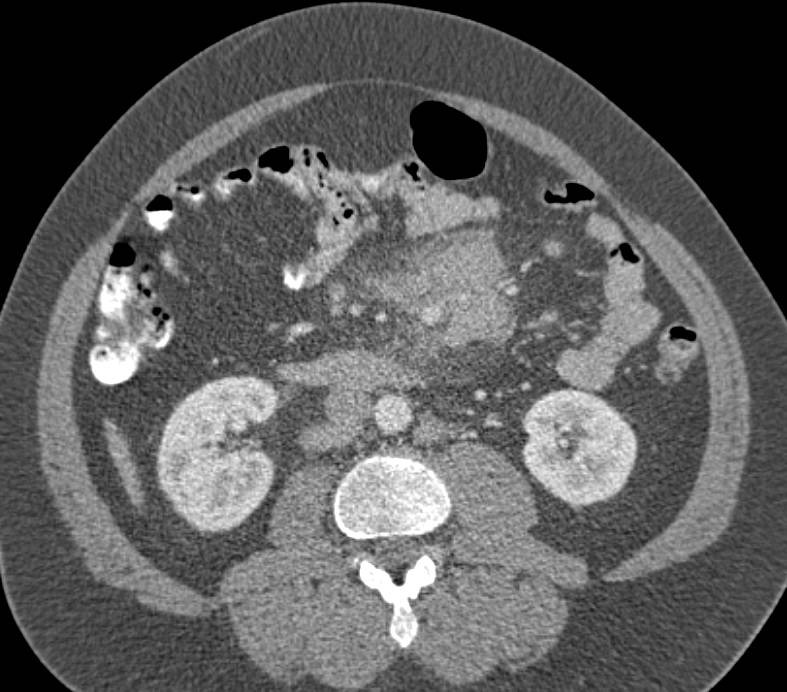

Acute Cholecystitis in a Patient with Vessel Encasement due to Panceatic Cancer. The PV/SMV confluence is especially encased